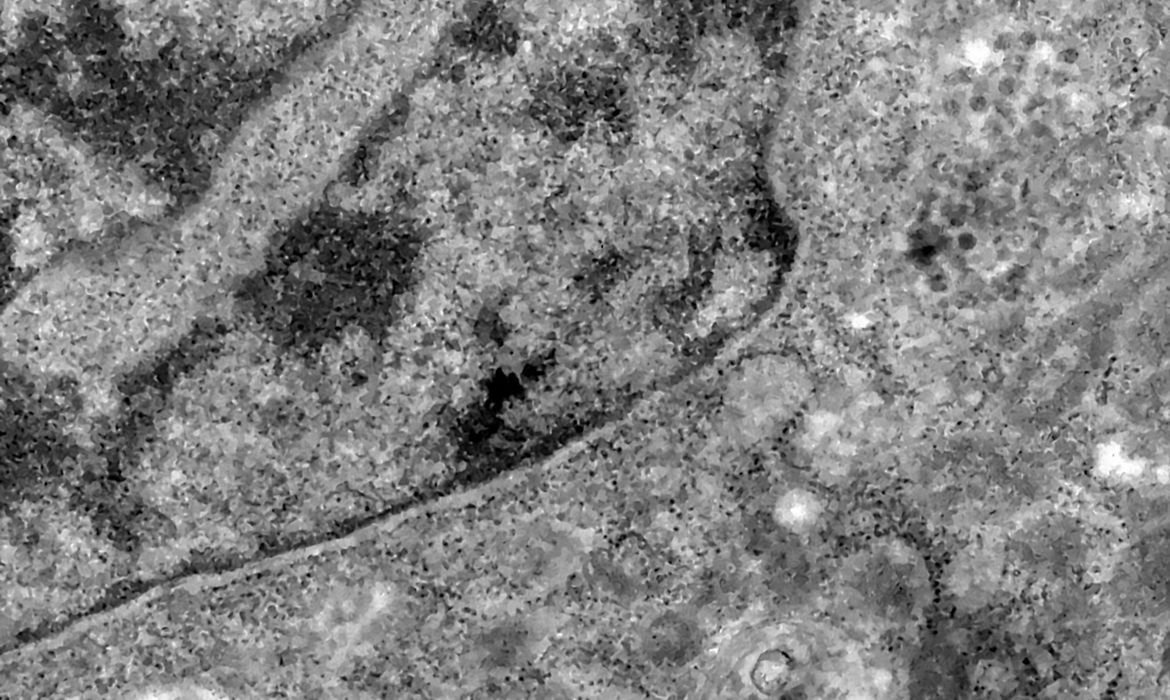

Foto: Debora Barreto/Fiocruz